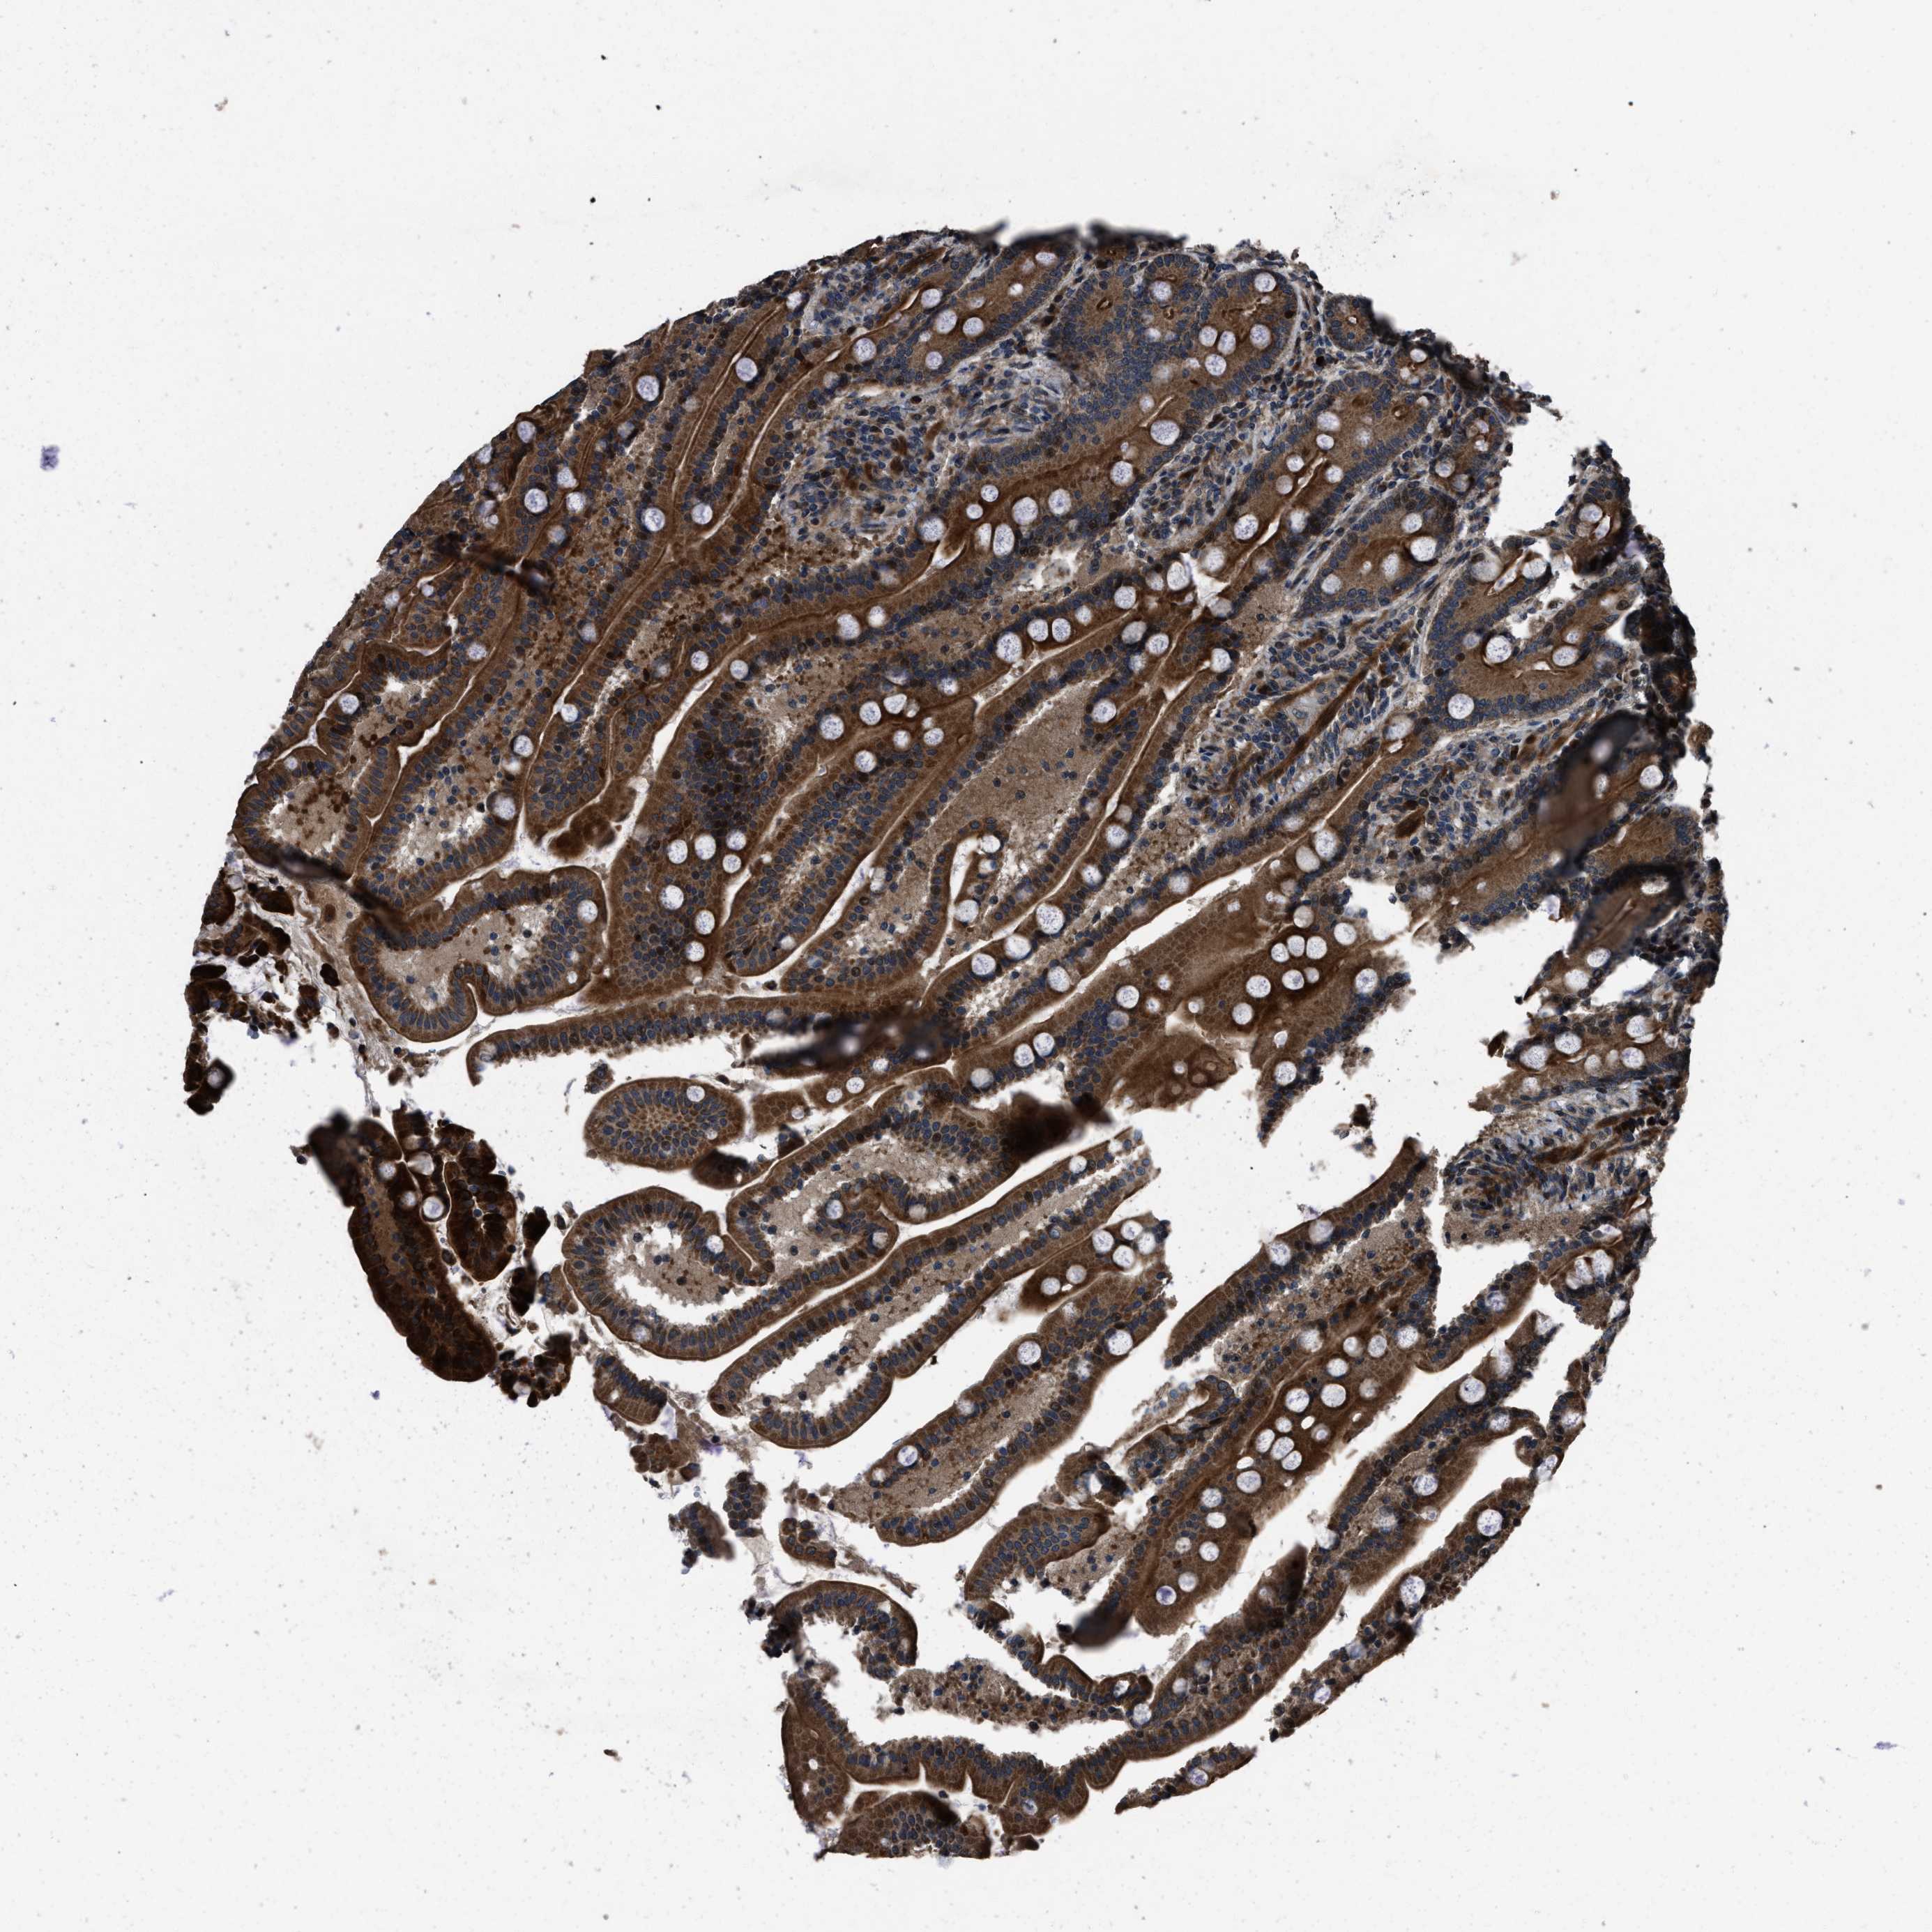

NSD3